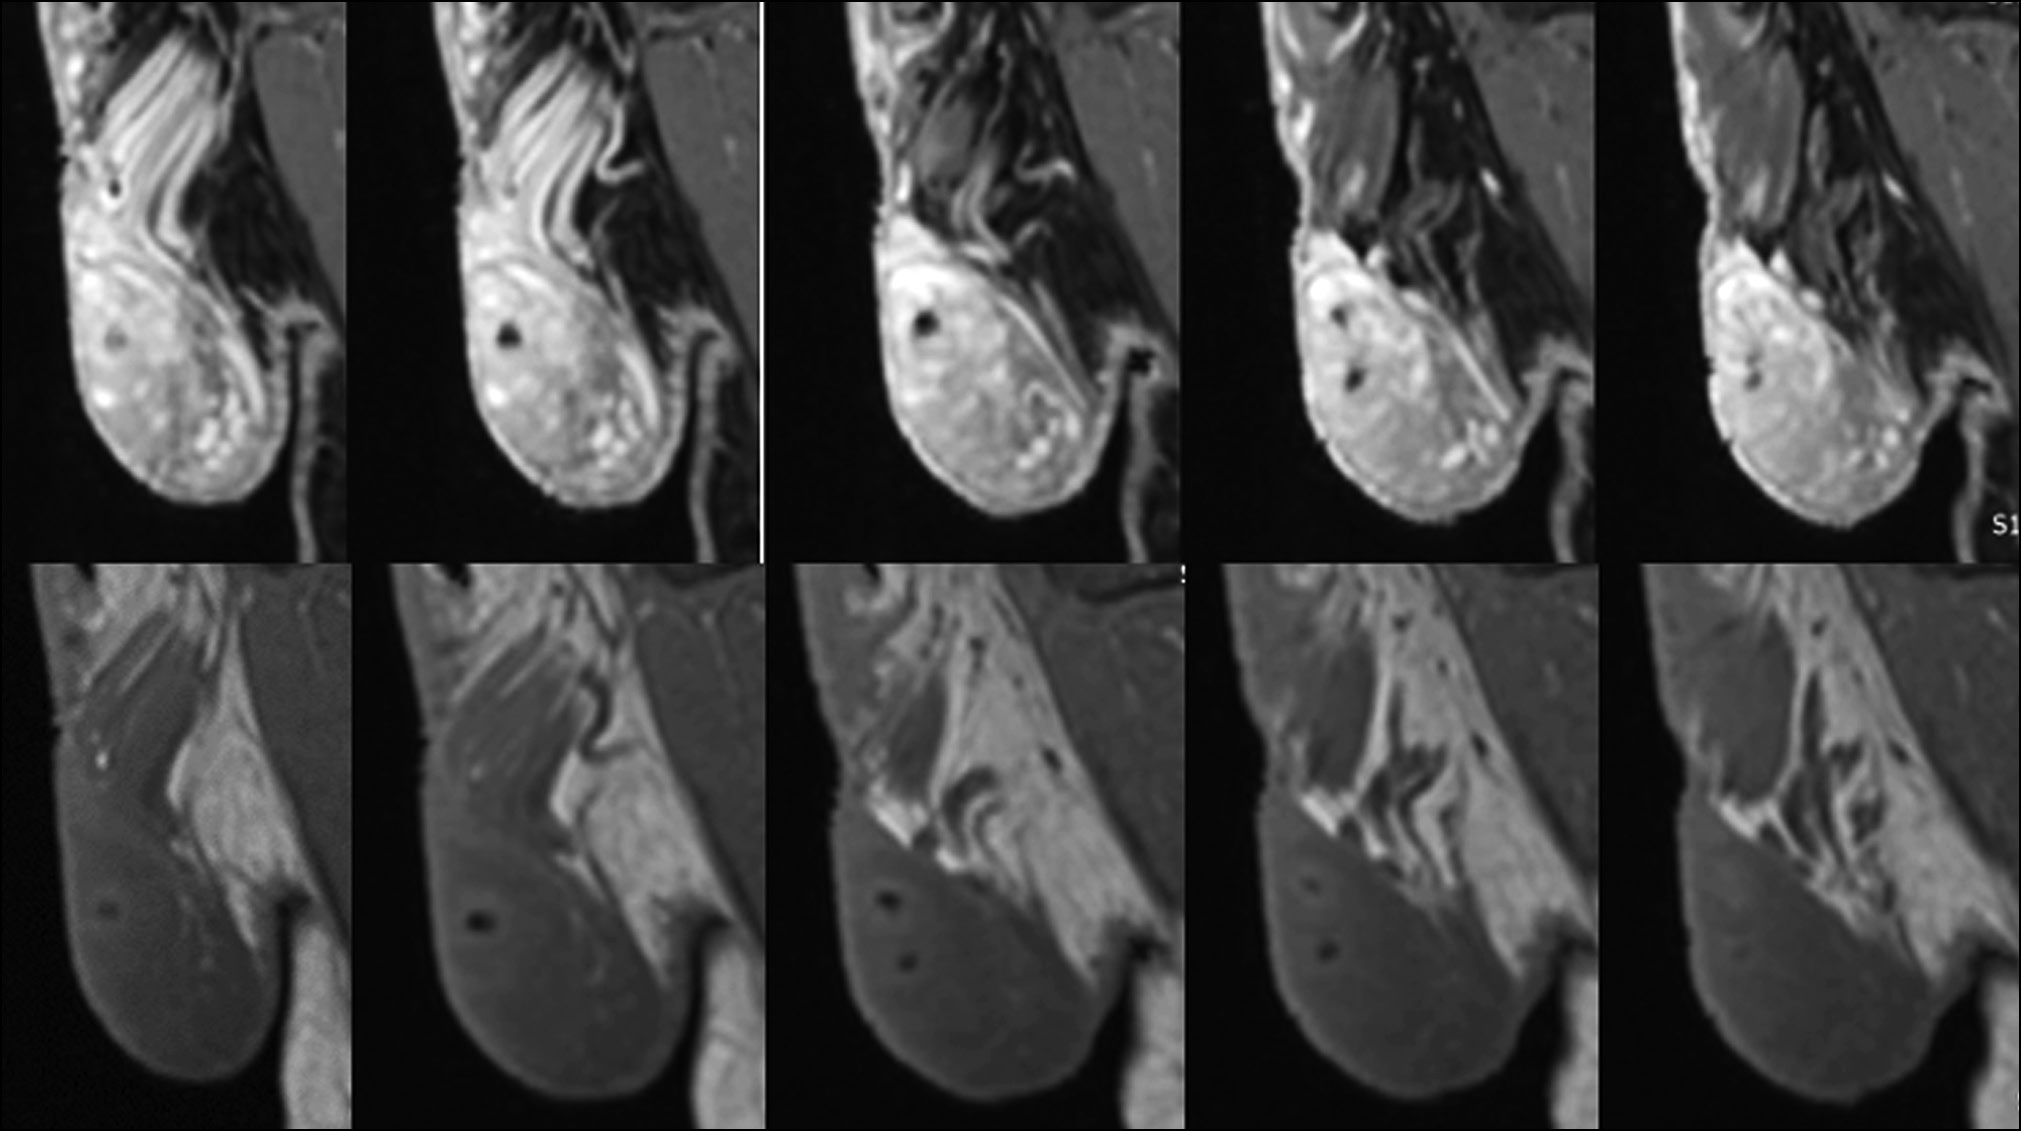

Рис. 7. Две группы изображений ишемизированной области левого яичка на разных уровнях. Верхние и нижние изображения получены в режимах STIR и T2 соответственно.

Рис. 8. Левостороннее варикоцеле при наличии тонкого слоя гидроцеле.